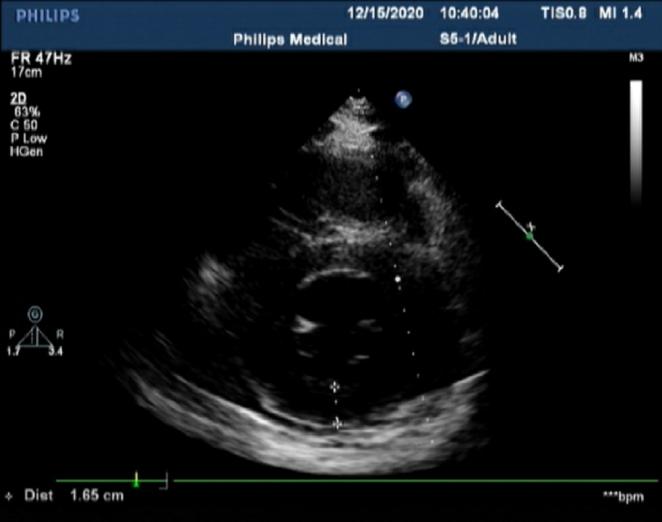

王福军主任及罗亚雄主任查房后分析患者无肥胖、肺气肿及大量心包积液等,心脏外因素所致心电信号传导受阻所致低电压可能小。而患者心肌均匀增厚,有限制表现,心肌内异常物质的浸润或贮积所致低电压可能性大,如心脏淀粉样变性、铁超负荷、溶酶体或糖原贮积等。患者心脏超声虽未见心肌内颗粒样强回声影,但淀粉样变性不能完全排除,进一步完善心脏磁共振见左室心肌存在明显的钆延迟强化。

图3.心脏磁共振心肌增厚,左室心肌明显钆延迟强化